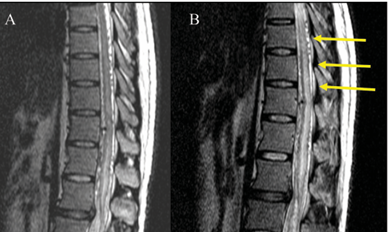

Background Spinal dural arteriovenous fistulas (sDAVFs) are one of the treatable causes of myelopathy, resulting from venous hypertension, cord edema, and resultant ischemia. Steroids might induce abrupt neurological deterioration, presumably...